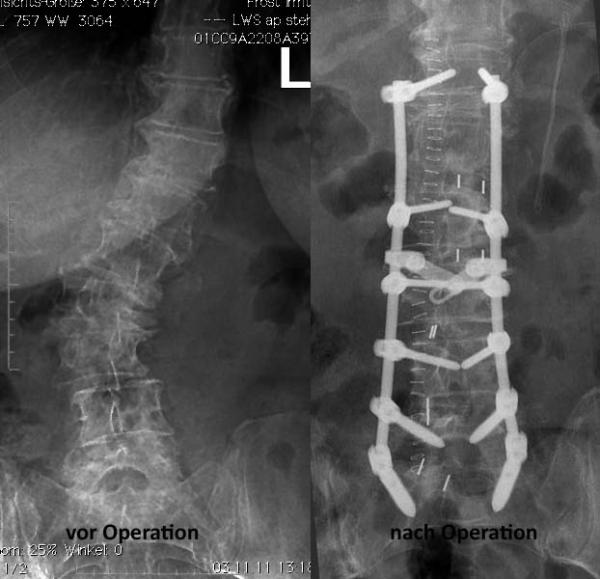

Das Ziel einer Operation ist die Beseitigung der Schmerzen. Dies erfolgt durch die Wiederherstellung der Wirbelsäulenbalance und die Dekompression von Nerven sowie eine eventuelle Erweiterung des Wirbelkanals. Mit Hilfe von Schrauben-Stab-Systemen kann das Lot der Wirbelsäule wiederhergestellt und die Wirbelsäule stabilisiert werden. Dadurch wird der Verschleißprozeß an den Gelenken (Spondylarthrose) und den Bandscheiben (Osteochondrose) mit den begleitenden schmerzhaften Entzündungsreaktion gestoppt. Die Operation erfolgt in minimalinvasiver, mikrochirurgischer Technik, d. h. ohne große Schädigung des umgebenden Gewebes und der umgebenden Strukturen. Der Patient kann selbst bei ausgedehnten Operation bereits am gleichen Tag aufstehen und nach 7-10 Tagen entlassen werden. Im Anschluß ist eine intesive krankengymnastische Nachbetreuung für 6 -12 Wochen erforderlich, um die Muskulatur und die Gelenke an die durchgeführte Korrektur anzupassen. Diese "Anpassungsphase" erfordert häufig noch eine begleitende Schmerzmedikation. Im weiteren Verlauf is auch eine Rehabilitationskur sinnvoll, wo konzentriert in 3-4 Wochen ein Muskelaufbautraining erfolgt.